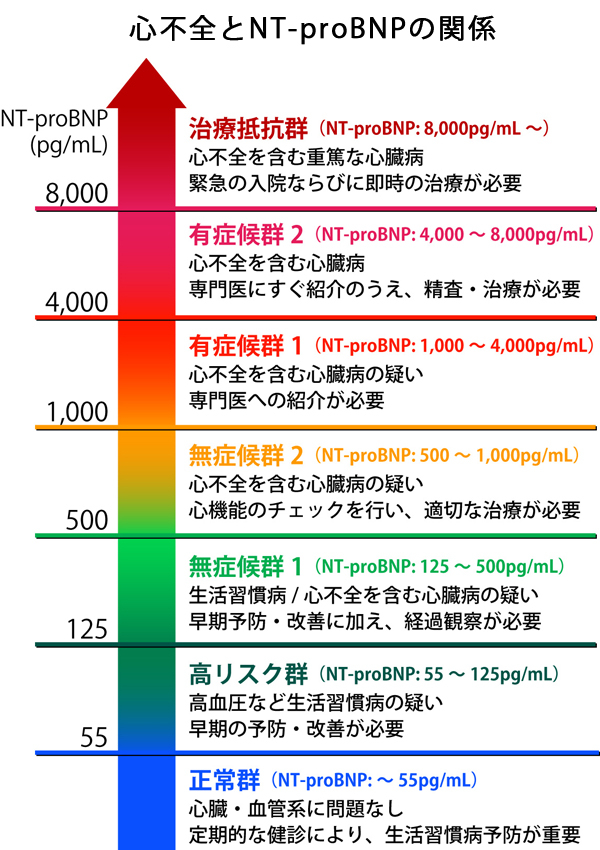

◆心機能検査 2,000円(税抜)

心機能不全の初期で、あまり症状がない場合、心電図だけでは発見できない場合もあり、NT-proBMP検査も合わせて行うことで、心臓病の早期発見につながります。

検査方法・・・採血したものを検査します。

お勧めする方・・・息切れ、動悸、脚のむくみ、冷え症、めまい等の症状のある方